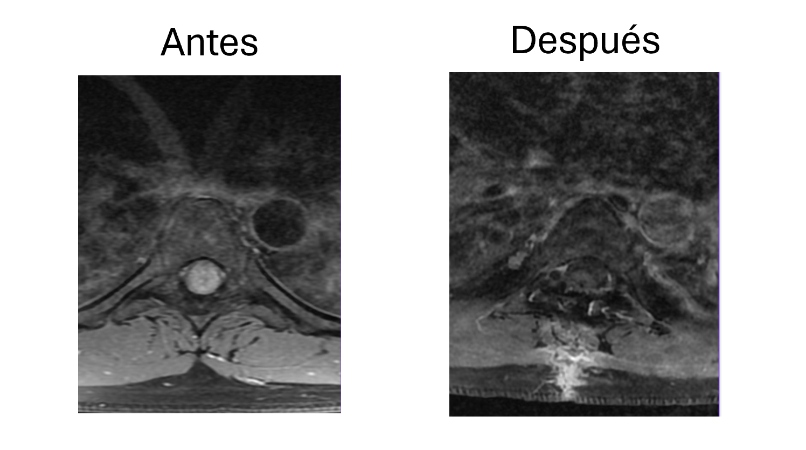

Abordaje cervical anterior con colocación de caja intersomatica C5-C6

Después de años con dolor intenso y limitación en el cuello, me realizaron un abordaje cervical anterior con colocación de caja intersomática en C5-C6. La recuperación fue rápida y el alivio fue casi inmediato. Volví a mis actividades sin molestias. Estoy muy agradecido con el equipo médico.